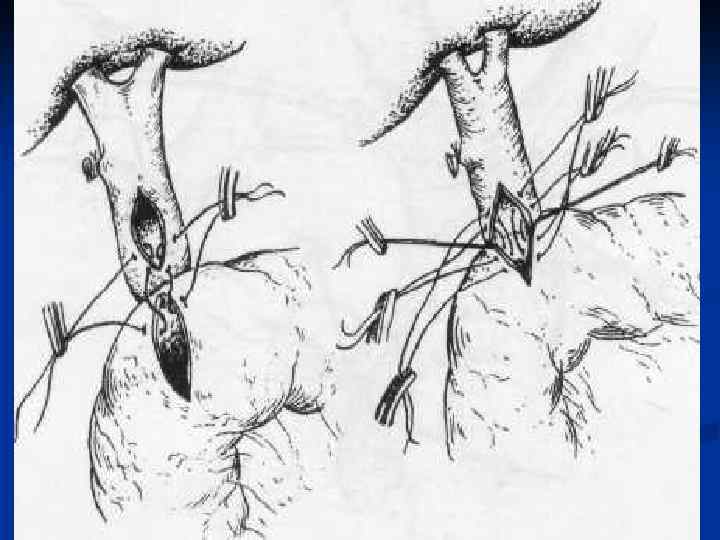

I. Восстановительные операции (восстановление проходимости протоков) 1. Эндобилиарные вмешательства под УЗИ или R – контролем (бужирование, баллонная дилатация, стентирование протоков). 2. Пластика стриктуры 3. Иссечение стриктуры с наложением анастомоза. II. Реконструктивные операции (наложение билиодигестивных анастомозов) 1. Анастомозы внепеченочных желчных протоков: а) с двенадцатиперстной кишкой (ХДА) б) с тощей кишкой (гепатико-, холедохоеюноанастомозы по Ру или по Брауну). 2. Анастомозы внутрипеченочных желчных протоков с сегментом тощей кишки, выключенной по Ру или желудком при высоких стриктурах

I. Восстановительные операции (восстановление проходимости протоков) 1. Эндобилиарные вмешательства под УЗИ или R – контролем (бужирование, баллонная дилатация, стентирование протоков). 2. Пластика стриктуры 3. Иссечение стриктуры с наложением анастомоза. II. Реконструктивные операции (наложение билиодигестивных анастомозов) 1. Анастомозы внепеченочных желчных протоков: а) с двенадцатиперстной кишкой (ХДА) б) с тощей кишкой (гепатико-, холедохоеюноанастомозы по Ру или по Брауну). 2. Анастомозы внутрипеченочных желчных протоков с сегментом тощей кишки, выключенной по Ру или желудком при высоких стриктурах